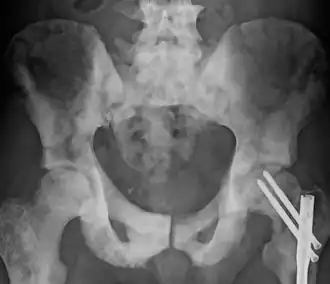

Остеосклероз — патологическое состояние, повышение костной плотности, проявляющееся в виде утолщения костных трабекул и компактного вещества кости. Губчатая кость при остеосклерозе приобретает узкопетлистую структуру. В связи с тем, что уплотнённая костная ткань становится менее прозрачной по отношению к рентгеновским лучам, остеосклероз может выявляться при рентгенологических методах исследования. Различают физиологический остеосклероз (отмечаемый в процессе роста скелета в области ростковых зон) и патологический остеосклероз.[1] В числе заболеваний, сопровождающихся остеосклерозом — мелореостоз, остеопетроз, остеопойкилоз, хронический идиопатический миелофиброз и др. Субхондральный остеосклероз является одним из проявлений остеоартроза.